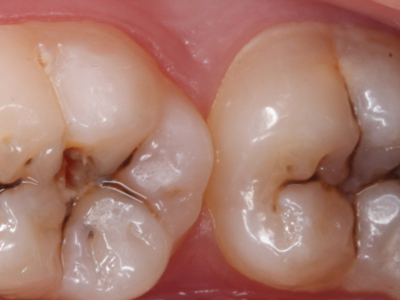

年轻恒牙龋好发于第一、二恒磨牙(牙合)面、邻面,上颌中切牙邻面,多为急性龋,龋坏进展快。平滑面的早期龋多为白垩色的斑片,点隙窝沟的早期龋多为浸墨状,表面粗糙。如果早期龋不及时治疗,可逐渐形成大而深的龋洞,易导致牙髓炎和根尖周炎。

年轻恒牙龋一般可进行充填治疗,对于早期的年轻恒磨牙,提倡采用微创的预防性树脂充填术、改良的预防性树脂充填术;深龋必要时考虑二次去腐修复。日常注意饮食,重视口腔卫生,考虑局部使用氟化物防龋,如含氟牙膏、含氟漱口水等,进行预防。对于年轻恒磨牙,可早期进行窝沟封闭,定期进行口腔检查。